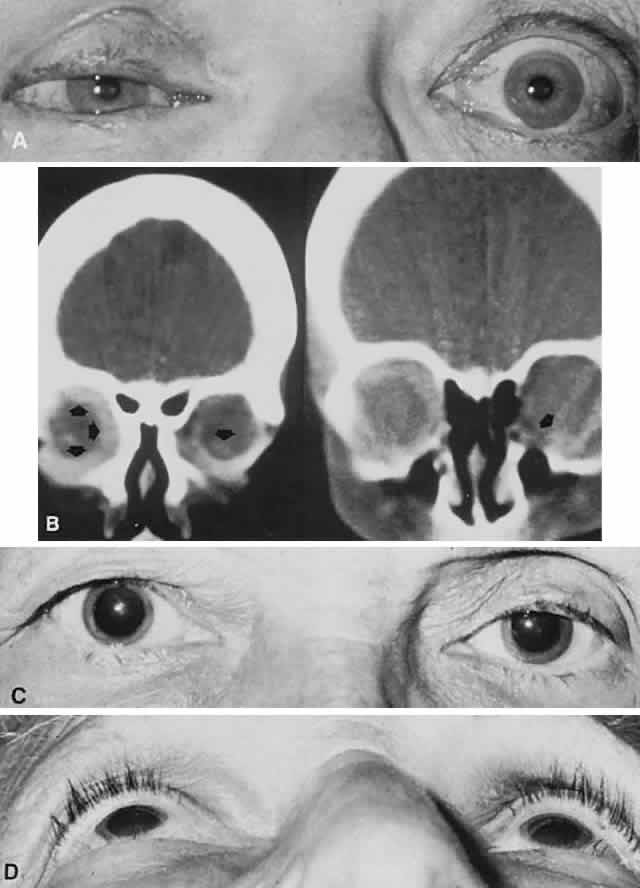

Fig. 9. Enophthalmos. A. A 56-year-old woman with right enophthalmos and fixation of the globe, and proptosis of the left eye. B. Bilateral orbital metastases of scirrhous breast carcinoma were disclosed by CT scan. C. Patient was referred for right proptosis but actually had left enophthalmos caused by simple senile atrophy of orbital fat pad, without history of facial trauma; note sunken superior lid sulcus on left (C), and relative position of left globe and lids, as viewed from below (D).